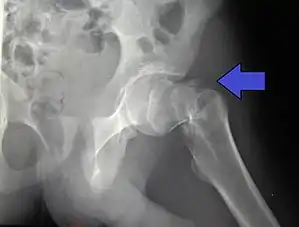

Displaced fractures of the trochanter or femoral neck will classically cause external rotation and shortening of the leg when the patient is laying supine.[5]

Typically, radiographs are taken of the hip from the front (AP view), and side (lateral view). Frog leg views are to be avoided, as they may cause severe pain and further displace the fracture.[5] In situations where a hip fracture is suspected but not obvious on x-ray, an MRI is the next test of choice. If an MRI is not available or the patient can not be placed into the scanner a CT may be used as a substitute. MRI sensitivity for radiographically occult fracture is greater than CT. Bone scan is another useful alternative however substantial drawbacks include decreased sensitivity, early false negative results and decreased conspicuity of findings due to age-related metabolic changes in the elderly.[16]

X-rays of the affected hip usually make the diagnosis obvious; AP (anteroposterior) and lateral views should be obtained.